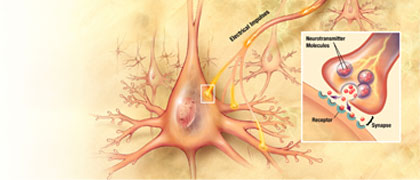

Alzheimer's Disease Education and Referral Center, a service of the National Institute on Aging